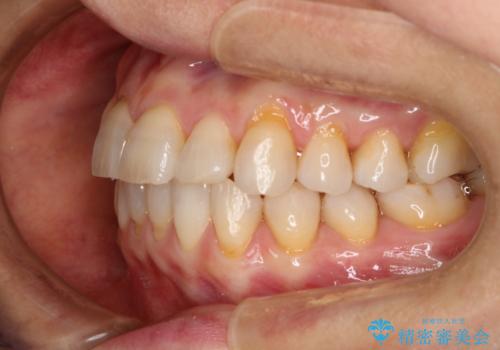

前歯の反対咬合、奥に引っ込んでしまっている歯をインビザラインで治療する

- インビザラインでの治療を希望した患者様です。

上の前歯の反対咬合があり、治療の途中で下の前歯を乗り越える必要があります。

前歯を乗り越える治療はワイヤーの方が有利ではありますが、インビザライン単独でも行うことができます。

患者様によっては乗り越えるタイミングだけワイヤーを装着し、そのあとでまたインビザラインに戻るという方もいらっしゃいます。